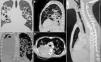

Papilomatosis respiratoria recurrente con compromiso pulmonar y de la pared torácica: una rara complicación en un adolescente

Recurrent respiratory papillomatosis with lung and chest wall involvement: A rare complication in an adolescent